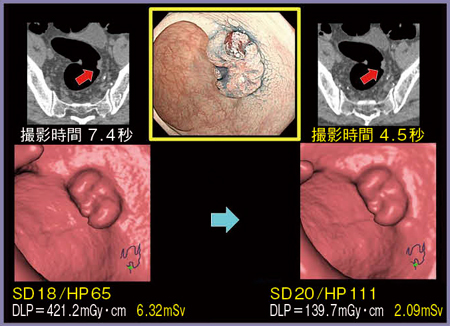

■症例1:HP111での撮影(図1)

当院では通常,術前の大腸CTにヘリカルピッチ(HP)65を使用しており,撮影時間は7.4秒となる。16列装置と比べると約半分の時間となっているが,さらにHP111を使用することで,撮影時間を4.5秒にまで短縮することができた。

また,AIDR 3Dを使用して線量を低減しているが,病変部位を十分に指摘でき,アキシャル画像においても遜色のない画像を得ることができた。

図1 症例1: HP111での大腸CT

撮影時間を4.5秒に短縮可能